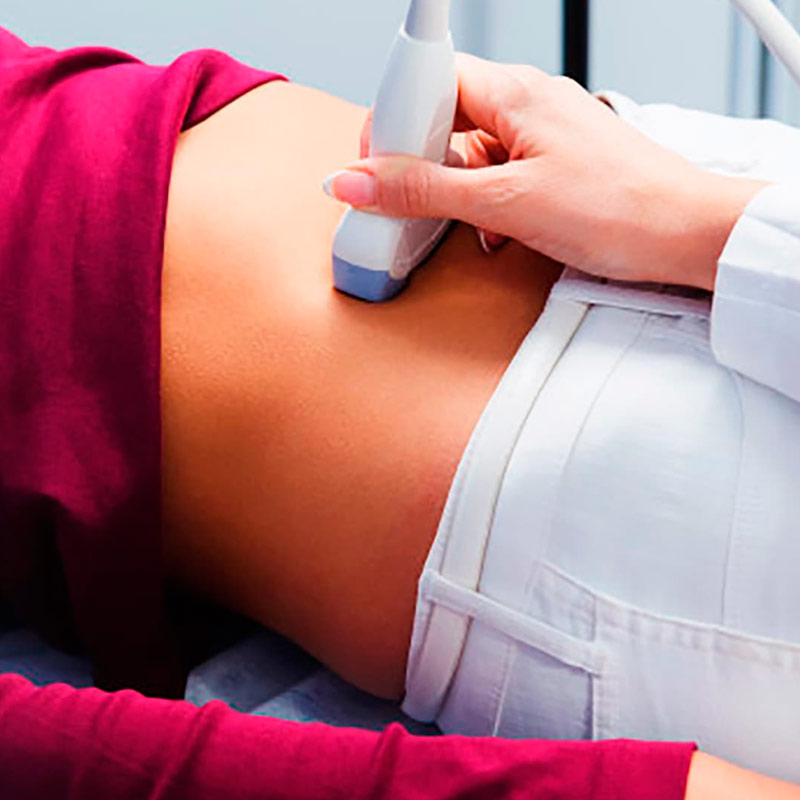

Campo de la medicina que se especializa en la atención de las mujeres durante el embarazo y el parto, y en el diagnóstico y tratamiento de enfermedades de los órganos reproductivos femeninos.